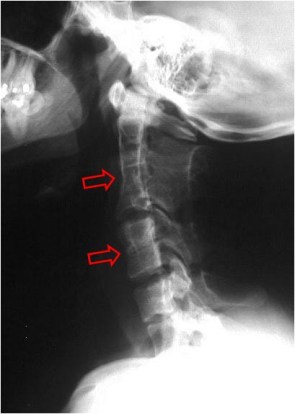

SIGNO DE LA CUERDA COMBADA

Signo de enfermedad de Legg-Calvé-Perthes (osteonecrosis de la cabeza femoral) evolucionada. Consiste en la existencia de una línea curva radiodensa en la base del cuello femoral (flecha) que, probablemente, representa el borde anterior o lateral de una cabeza femoral severamente deformada.